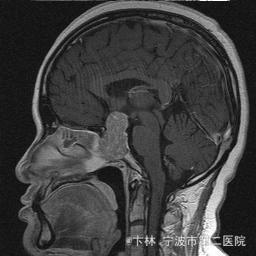

40岁女性,因“双眼视力下降三月余伴停经1个月余”入院。 患者三月前无明显诱因下出现双眼视力下降,视物模糊,尤以左眼为甚,只能近距离看到手动,无头痛、头晕,无恶心、呕吐,无视物旋转,无行走困难等不适,患者曾在某眼科医院就诊治疗,考虑为双眼视神经炎,予以营养,补液对症等治疗(具体不详),情况不见好转,近一月来患者月经停止,来我院神经外科门诊,予以查头颅CT,头颅MRI,提示“垂体大腺瘤”,为求进一步治疗收住入院

予以完善血,尿,粪常规检查,及凝血功能全套,输血功能全套及垂体功能全套,蝶鞍冠状CT等术前检查措施,行经蝶入路垂体瘤切除术。术后予以对症,补液,调节血电解质等治疗,患者视力明显改善,复查头颅MRI提示肿瘤基本全切,一周后患者出院。

此病人颅内垂体瘤体积较大,突破鞍隔压迫视交叉,故患者视力视野障碍为首发症状,该肿瘤主体有大部分向蝶窦腔生长,因此采用经蝶手术入路,肿瘤切除满意,术后患者视力视野恢复满意,。